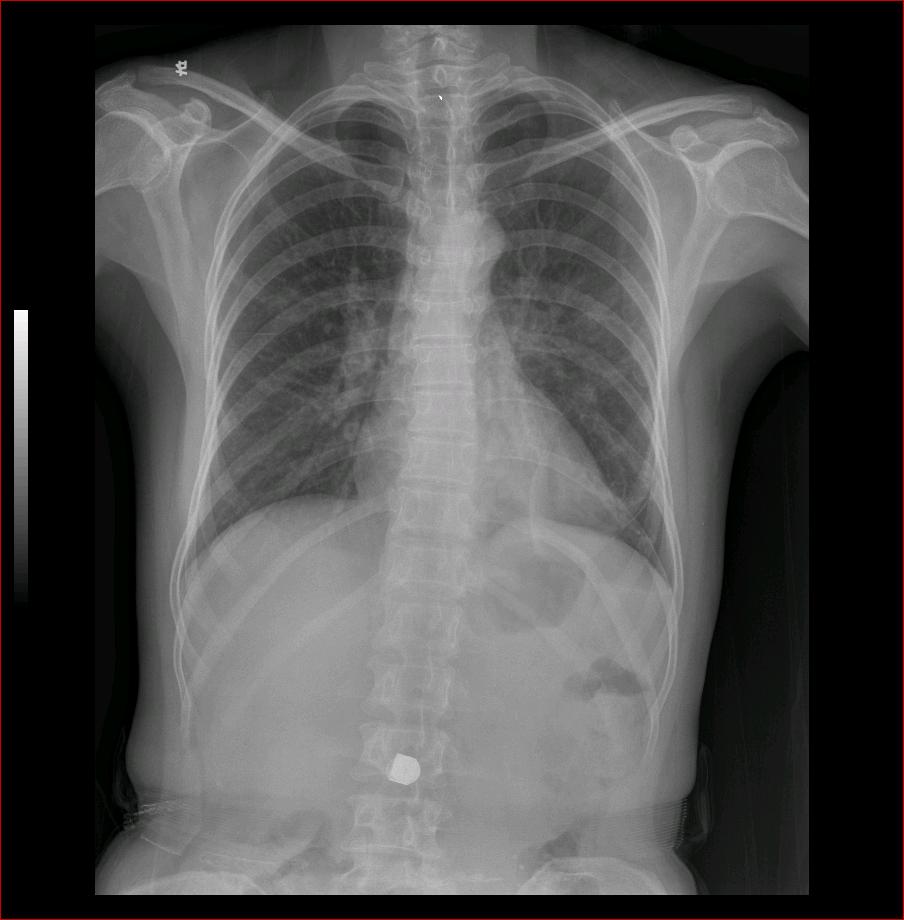

标题: X2653:女,50岁,咳嗽,发热,38度,

左下肺斑片状高密度影,与脊柱重叠,边缘模糊,正位看肺门不大。侧位看似有肿块。考虑炎症。ct待排占位。

左中、下肺野见斑片状密度增高影,边缘较模糊,左肺门影增大,侧位呈块状。

考虑:1、左肺感染性病变,建议治疗后复查。

2、左侧占位性病变,建议作ct检查。

左侧中心型肺癌并阻塞性肺炎可能性大,建议ct检查。